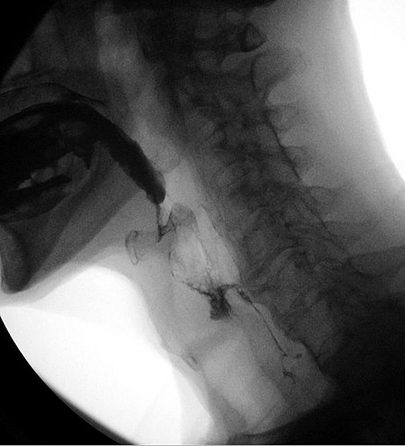

Βιντεοφθοροσκοπική μελέτη κατάποσης (VFSS).

Η βιντεοφθοροσκοπική μελέτη κατάποσης (VFSS), γνωστή και ως τροποποιημένη κατάποση βαρίου, είναι μια δυναμική ακτινογραφική εξέταση της στοματικής κοιλότητας, του φάρυγγα και του οισοφάγου. Η VFSS επιτρέπει την αξιολόγηση της λειτουργίας της κατάποσης του ασθενούς μέσω της χορήγησης υγρών και στερεών διαφορετικής σύστασης για την αξιολόγηση της κατάποσης με φθοριοσκοπική.